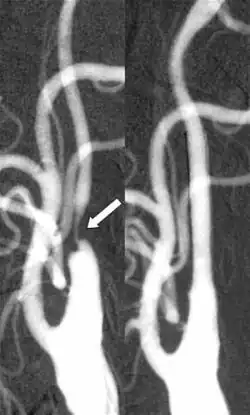

Der Zugang zur arteriellen Zirkulation kann entweder durch eine transfemorale/transradiale Punktion oder durch eine direkte Punktion der Halsschlagader gewonnen werden. Nachher wird der Stent in die enge Stelle eingebracht und falls nötig, mit einem Ballon ausgebreitet, um den Fluss in der Arterie wieder herzustellen. Zu den kritischsten Momenten der Behandlung gehören: Gewinnen des arteriellen Zugangs, Passage des Stenose mit einem Draht, Einbringen des Stents über die Läsion. Um die Behandlungsrisiken in Form von Embolisation zu reduzieren, können mehrere weitere Schritte während der Intervention erfolgen (z. B. Einbringen eines Filters in die Arterie). Eine Embolisation des Thrombus kann auch nach der Behandlung auftreten. Deswegen wird aktuell eine neue Generation von zweischichtigen Stents entwickelt, um dies zu verhindern.[5]